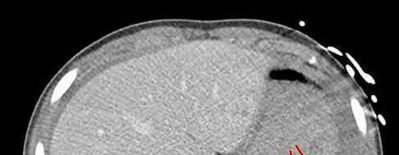

A 15-year-old boy presents with a permeative lytic lesion in the femoral diaphysis with aggressive periosteal reaction ('onion skinning'). Biopsy reveals uniform small round blue cells. Cytogenetic analysis of this tumor will most likely demonstrate which of the following translocations?

Explanation

The clinical and radiographic description is classic for Ewing sarcoma. The characteristic cytogenetic abnormality is a balanced translocation t(11;22)(q24;q12), which fuses the EWS gene on chromosome 22 with the FLI1 gene on chromosome 11. This is seen in approximately 85-90% of Ewing sarcomas. t(9;22) is the Philadelphia chromosome (CML), t(X;18) is seen in synovial sarcoma, t(2;13) in alveolar rhabdomyosarcoma, and t(12;16) in myxoid liposarcoma.